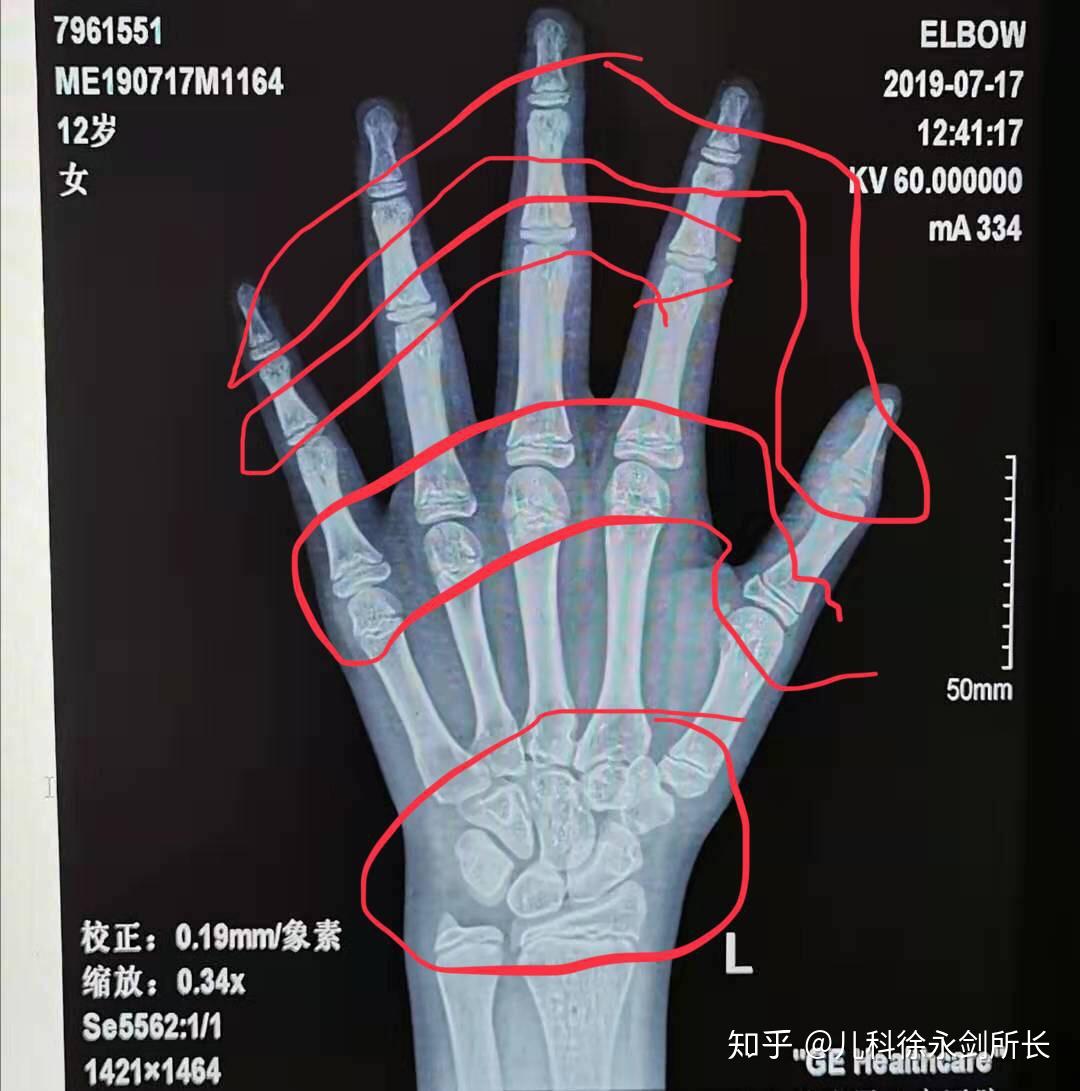

简介:骨龄是骨骼年龄的简称,需要借助于骨骼在X光摄像中的特定图像来确定。通常要拍摄左手手腕部位的X光片,医